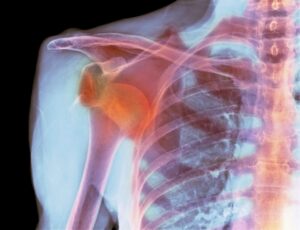

Shoulder dislocation is one of the most common types of dislocation. The shoulder joint can easily dislocate because it has a wide range of motion. Sudden twists and collisions in the knee can cause the kneecap to dislocate. Elbow dislocation usually occurs when the hands rest on the ground during a fall. Finger dislocations are especially common in athletes. The joint can dislocate when the finger is strained. The jaw joint can dislocate as a result of very wide mouth opening movements or trauma.

The doctor examines the dislocated joint and checks its range of motion. X-rays are used to see if the joint surfaces have shifted. MRIs provide more detailed information about the ligaments, muscles, and cartilage. CT scans are used to evaluate bone structure damage in detail.